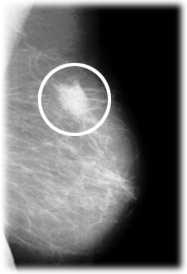

Das Bild zeigt einen krebsverdächtigen Knoten in der Brust.Die Mammographie ist eine Röntgenuntersuchung der Brust.

Die Abbildung zeigt einen krebsverdächtigen Knoten in der linken Brust.